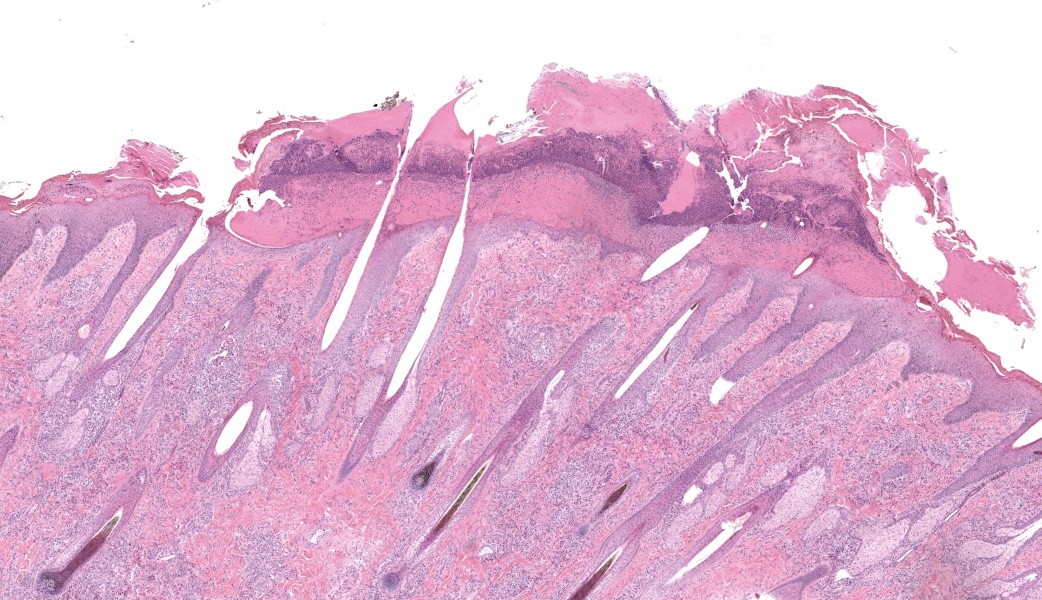

Haired skin, coronary band. Expanding and infiltrating the entire dermis are multifocal to coalescing perivascular, periadnexal and interstitial aggregates of moderate numbers of lymphocytes, eosinophils and histiocytes, fewer plasma cells and occasional neutrophils. Multifocally within dermis are few small areas of intensely eosinophilic, fragmented collagen fibers admixed with eosinophilic cellular- and basophilic nuclear debris, surrounded by epitheloid macrophages and multinucleated giant cells (eosinophilic granulomas). Intramurally and intraluminally within multiple hair follicles are moderate numbers of eosinophils, lymphocytes and histiocytes and few multinucleated giant cells (mural and luminal folliculitis), and adjacent follicular epithelium display moderate spongiosis. In the dermal-epidermal interface, there is a multifocal mild edema. The epidermis shows mild lymphocytic infiltration, mild spongiosis and occasional apoptotic keratinocyte, diffuse mild acanthosis and mild rete ridge formation (epidermal hyperplasia), moderate parakeratotic and orthokeratotic hyperkeratosis and multifocal erosions and ulcerations, the latter being covered by large serocellular crusts spanning over several adnexal units. Serocellular crusts show abundant viable and degenerated neutrophils, occasional eosinophil, cellular debris, fibrin, free keratin and hair fragments and occasional small basophilic bacterial colonies. There are also small epidermal intracorneal pustules multifocally. Several arteriolar walls in deep dermis show infiltration of few eosinophils and lymphocytes (vasculitis). The deep dermis displays mild diffuse edema.Contributor's Morphologic Diagnoses:

Haired skin, coronary band: Dermatitis and folliculitis, lymphoplasmacytic, histiocytic and eosinophilic, multifocal to coalescing, moderate, with eosinophilic granulomas, epidermal intracorneal pustules, serocellular crusts and orthokeratotic and parakeratotic hyperkeratosisEquine multisystemic eosinophilic epitheliotropic disease (MEED)

Equine multisystemic eosinophilic epitheliotropic disease (MEED) is a rare chronic disease and constitutes part of inflammatory bowel disease (IBD) in horses.13,15,17 MEED typically affects young Standardbred and Thoroughbred horses even though horses of older age and other breeds also may be affected.3,8,9,10,11,13,14,18,19,24 Seasonality with cases occurring in spring or summer is reported in some studies.11,14 Clinically, horses with MEED present with progressive weight loss, pitting edema, alopecia and exudative, exfoliative dermatitis characterized by scaling, crusting and skin ulcerations.3,6,10,11,13,14 Lesions often originate around coronary bands, sometimes with associated loss of chestnuts, and progressively becomes more generalized to also include head and the rest of the body.3,11,13,14 Most affected horses die or are euthanized within 8 months of diagnosis.13 In clinical cases described in the literature, pruritus is variably evident, as well as fever, diarrhea and peripheral eosinophilia.3,6,10,11,13,14,19 Peripheral eosinophilia is reported in approximately 14% of cases.3,13 Serum biochemical evidence of liver disease and/or hypoproteinemia may also be seen, and in a few cases, respiratory symptoms have been noted.3,6,8,9-11,18,19 In our case, there was no peripheral eosinophilia and no hypoproteinemia present at clinical work-up. Serum biochemistry was not investigated; hence, liver values were unknown.On postmortem examination, several organs are commonly affected in cases of MEED, including skin, pancreas, liver, common bile duct, gastrointestinal tract and lungs.13 Histologically, the disease is characterized by eosinophilic and lymphoplasmacytic infiltration, sometimes with eosinophilic granuloma formation.13 In the skin, various inflammatory patterns have been reported in MEED, including perivascular, lichenoid interface, interstitial, diffuse, and granulomatous.13,14 Eosinophils, lymphocytes and plasma cells are the main cellular elements.13,14 Other histological findings in the skin include epidermal hyperplasia, orthokeratotic and parakeratotic hyperkeratosis, epitheliotropic infiltration of eosinophils and lymphocytes, apoptotic keratinocytes, eosinophilic folliculitis, furunculosis, eosinophilic granulomas, and lymphoid nodules.13 Coagulated protein and collagen degeneration may be seen within deep dermal vessel walls.14 In our case, most of these lesions were present in examined sections of the skin. Within the gastrointestinal tract, lesions include ulcers on the tongue and/or within oral cavity, hyperkeratosis of the esophagus and non-glandular stomach, and mucosal ulcerations within the small and/or large intestine, as well as marked fibrosis in some organs, such as pancreas and liver; in the liver especially dissecting along bile ducts.11,14 Fibrosis may be so severe that loss of exocrine tissue is evident within pancreas, and in the liver, there may also be biliary hyperplasia.11,14 Lymph nodes may be enlarged due to eosinophilic infiltration, and increased numbers of eosinophils can be seen in bone marrow.6,9,13,14,18,19 In our case, all of these findings were present except oral ulcerations.

The contributor’s comment in this case provides an exceptional overview of multisystemic epitheliotropic eosinophilic disease (MEED) in horses and its major differentials, all of which were discussed during conference. MEED is currently considered to be an abnormal manifestation of inflammatory bowel disease (IBD) in horses. The cutaneous manifestation of MEED classifies as a perivascular dermatitis pattern, and the depth of inflammation and affected vasculature can assist with the diagnosis of MEED compared to others that would be confined more to the superficial dermis (i.e. insect bite hypersensitivity). Conference participants ultimately all agreed with the contributor’s diagnosis of MEED in this case.If lesions are restricted to the GI tract, other causes of inflammatory bowel disease, intestinal parasitism, and idiopathic focal eosinophilic enteritis (IFEE) should rise higher on the differentials list. There was an excellent case of IFEE seen earlier this year in Conference 1, Case 3, the contributor of which provided a fantastic comparison between IFEE and MEED in their comment. Additionally, a thorough overview of eosinophils was covered in the JPC comment for Conference 2, Case 3 this year as well, and those two comments are great supplementals to this case.